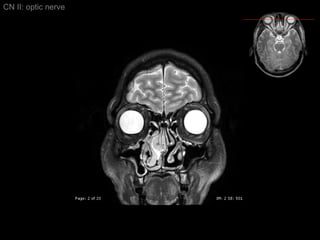

CN II: optic nerve Axial T2/ inferior to superior

CN II: optic nerve